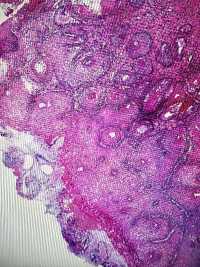

CIN1?

LSIL。

其实lsil的诊断一致性很低,上海的标准诊断lsil比较严格,似是而非者为非,本例属于似是而非,按我们的日常则争议比较多,我觉得综合看吧,阴道镜表现,hpv和tct检测结果来综合判断。

谢谢各位老师,TCT报ASCUS,患者自述HPV59阳